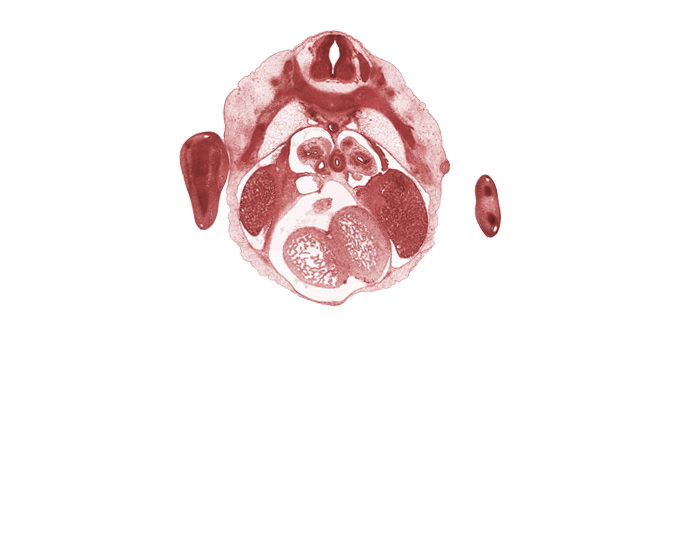

Carnegie Embryo #6520 | Location: 16-04-01

Keywords: T-5 spinal ganglion, central canal, dorsal meso-esophagus, edge of left horn of sinus venosus, epimere, inferior vena cava, interventricular septum, interventricular sulcus, left ventricle, lower secondary bronchus, mammary gland, neural arch, pericardial cavity, pleural cavity, rib 5, right ventricle

Source: The Virtual Human Embryo.